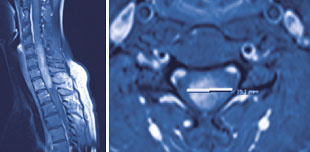

Abb. 3

Ausgedehnter Tumor des Rückenmarks innerhalb der Halswirbelsäule mit ausgeprägter Verdrängung des Rückenmarks.

Die in diesem Bereich der Rückenmarkshaut befindlichen Tumore liegen innerhalb des Markraumes (Abb. 3). Sehr selten handelt es sich um Ableger, Gefäss- oder Missbildungstumore. Gesamthaft bilden sie 5% aller spinalen Tumore, sie können aber im gesamten Rückenmark auftreten. Je nach Gewebetyp können sie scharf begrenzt oder ins Rückenmark wachsen und zeigen selten ein aggressives Wachstumsverhalten. Somit offenbaren sie sich durch unterschiedliche neurologische Ausfälle, wie beispielsweise durch Lähmungen, Missempfindungen, Gangunsicherheit oder auch durch Einschränkungen des Schliessmuskels der Blase und des Enddarms.